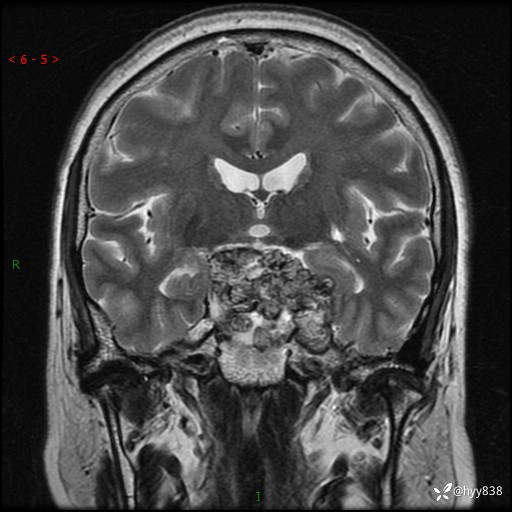

T2WI

鞍区MRI平扫

临床诊断:鞍区肿物